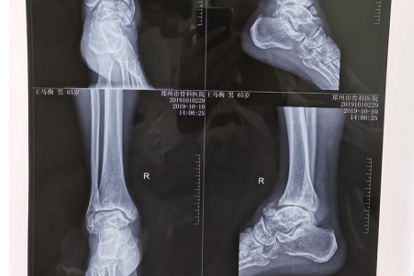

五、应力性骨折:容易被忽视的"隐形骨折"

1、特殊表现

疼痛逐渐加重,休息后缓解但一活动又出现。没有明显外伤史,X光早期可能看不出异常。

2、常见部位

第二、三跖骨是好发部位,多见于突然增加运动量的新手跑者。

3、处理原则

确诊后需要严格制动4-6周,使用步行靴或拐杖减轻负重。